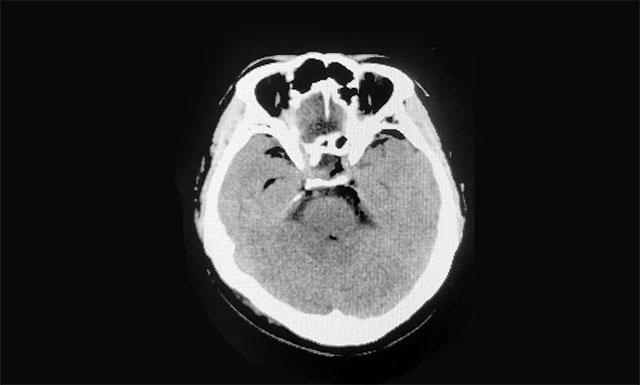

▲ 術(shù)后影像顯示腫瘤被切除